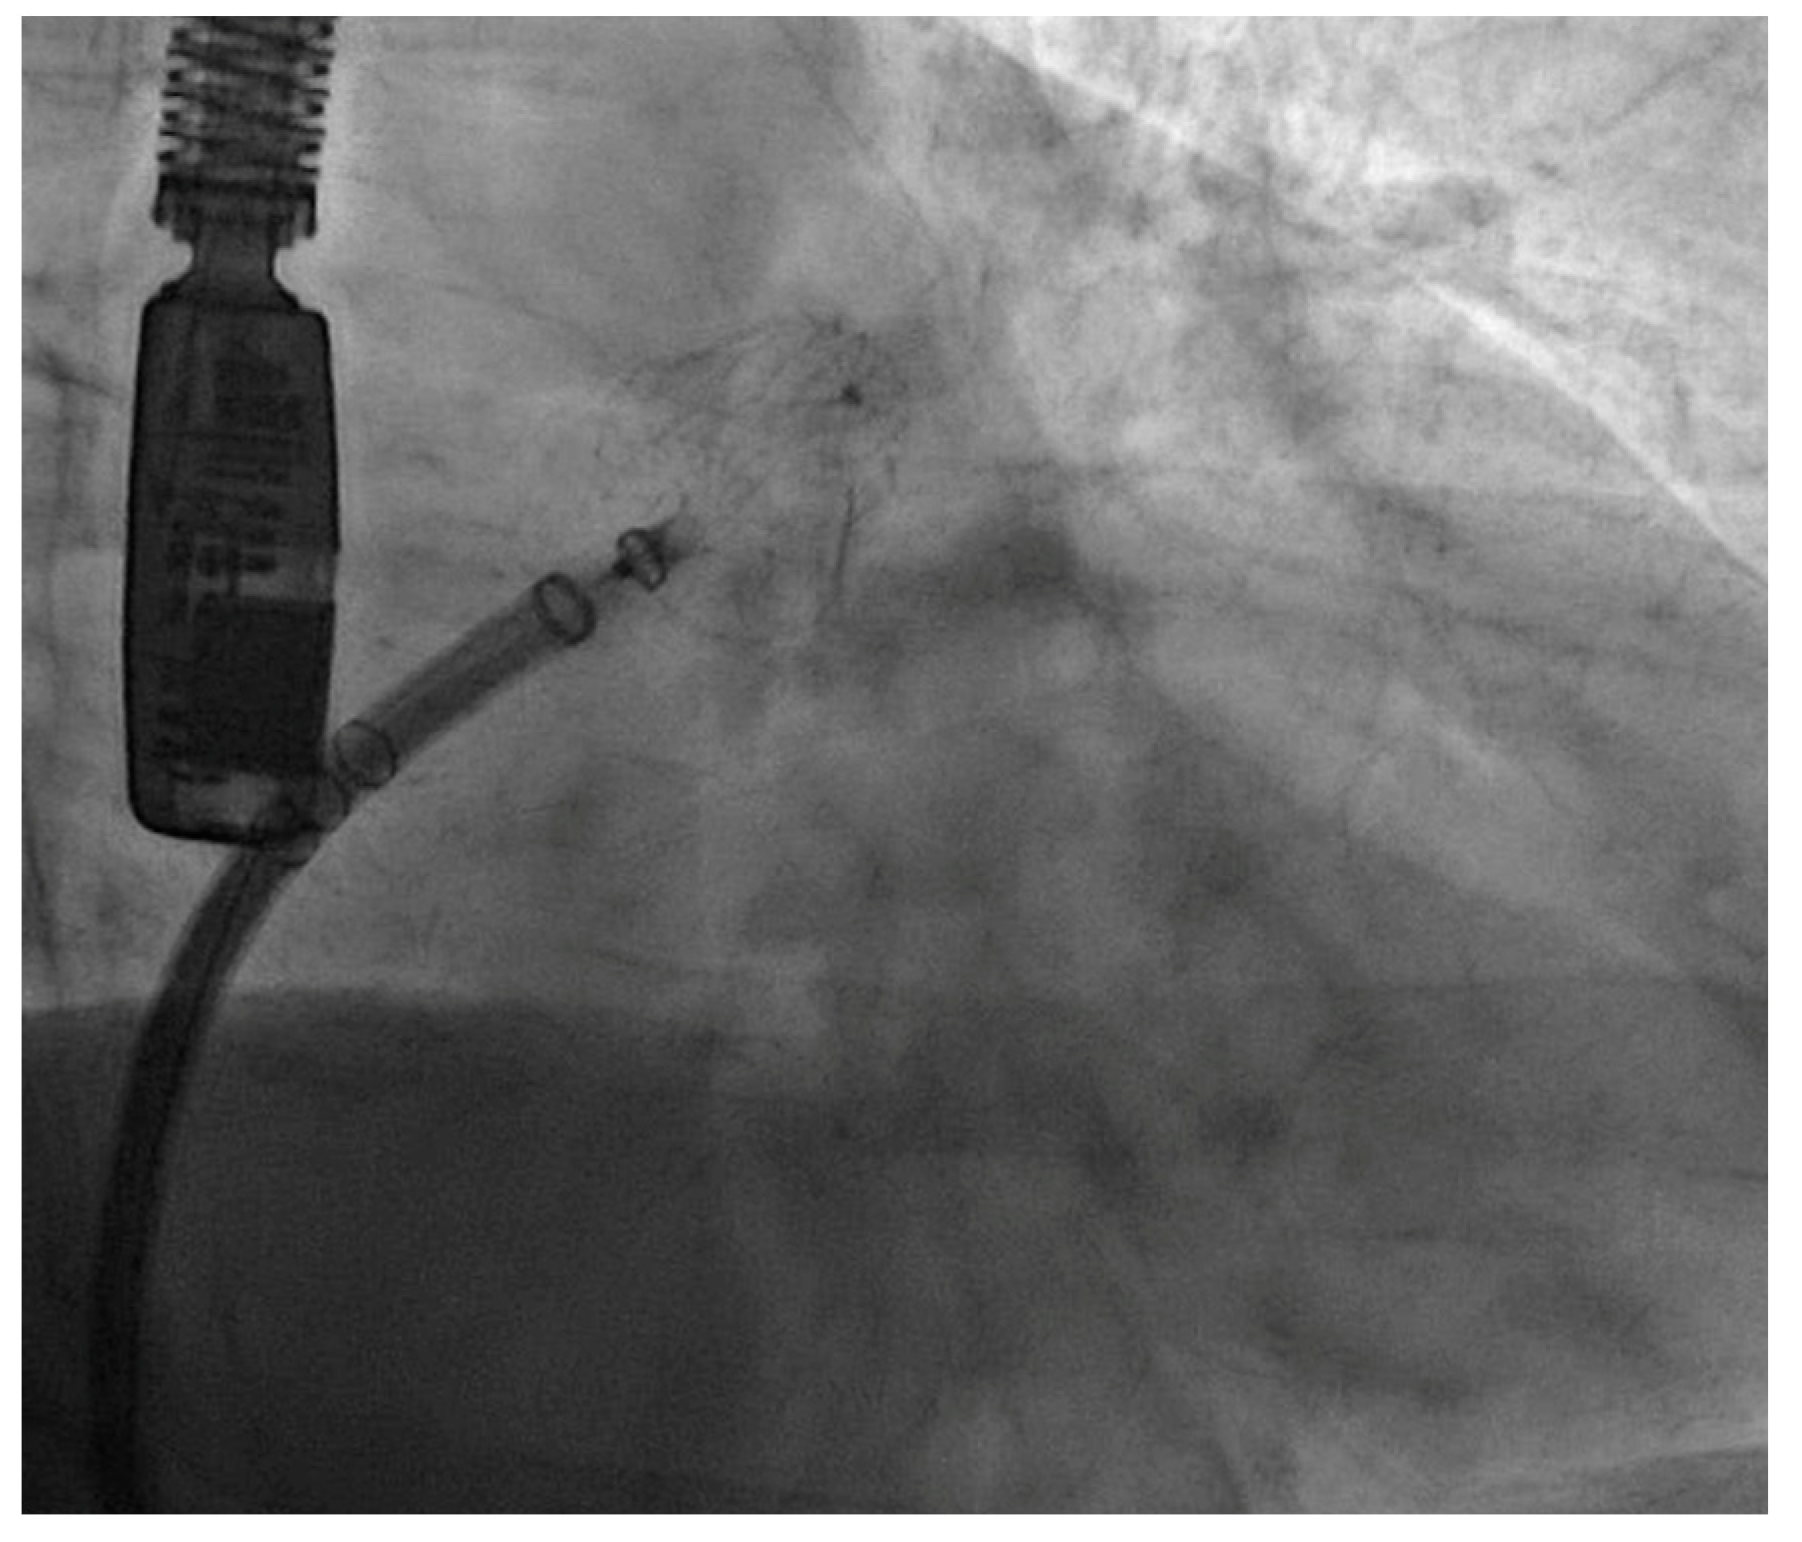

| LAAC device | Watchman FLX 27 mm | Watchman Flx 24 mm | Watchman Flx 24 mm | Watchman Flx 24 mm | Watchman FLX 24 mm | Watchman FLX 24 mm | Watchman FLX 31 mm | Watchman FLX 24 mm |